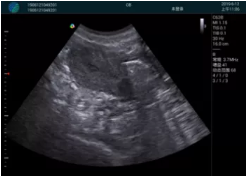

清晰顯示孕囊,通過軟件包計算孕齡7w+6d

M20實時引導,術(shù)中清晰顯示孕囊被破壞和抽吸針的過程,清晰顯示吸引針

抽吸結(jié)束后縱切子宮,孕囊已被完全抽吸,未見明顯殘留

橫切子宮,發(fā)現(xiàn)右側(cè)宮腔靠近宮角處有少許脫模樣殘留

M20引導下,抽吸針找到右側(cè)宮角處再次清掃

二次抽吸后再次進行超聲檢查,宮腔未見殘留,宮腔線清晰顯示